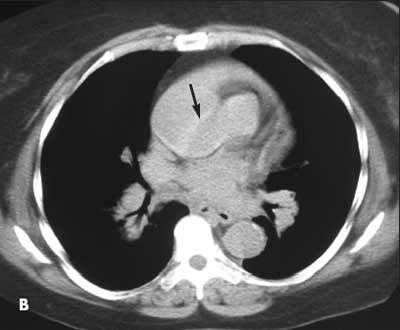

A 57-year-old woman presented with severe chest pain and general malaise. She had a history of hypertension. A frontal upright radiograph of the chest showed a prominent mediastinum at the upper limits of normal. The aorta was ectatic. A CT scan without contrast through the ascending aorta revealed a linear area of fluid within the ascending aorta (B, arrow). The fluid represents blood in the displaced intimal wall of the ascending aorta, which is diagnostic of aortic dissection.

Image courtesy of William Yaakob, MD and Stephen Schabel, MD.